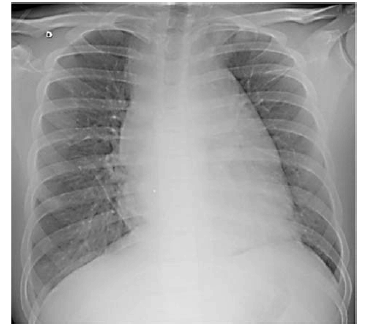

Paciente do sexo masculino, de 16 anos de idade, estudante, compareceu a consulta no posto de saúde, acompanhado da mãe, com queixa de dor no peito. Relatou início dos sintomas após colisão quando jogava futebol. O exame físico foi normal. A imagem a seguir mostra o Raio X do paciente, solicitado por insistência da mãe.

Considerando o caso clínico apresentado, julgue os itens a seguir.

Paciente do sexo masculino, de 16 anos de idade, estudante, compareceu a consulta no posto de saúde, acompanhado da mãe, com queixa de dor no peito. Relatou início dos sintomas após colisão quando jogava futebol. O exame físico foi normal. A imagem a seguir mostra o Raio X do paciente, solicitado por insistência da mãe.

Considerando o caso clínico apresentado, julgue os itens a seguir.

Paciente do sexo masculino, de 16 anos de idade, estudante, compareceu a consulta no posto de saúde, acompanhado da mãe, com queixa de dor no peito. Relatou início dos sintomas após colisão quando jogava futebol. O exame físico foi normal. A imagem a seguir mostra o Raio X do paciente, solicitado por insistência da mãe.

Considerando o caso clínico apresentado, julgue os itens a seguir.